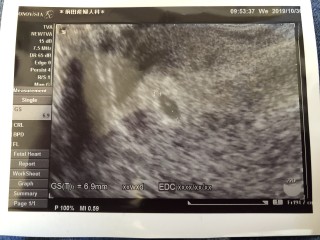

最終月経開始日が3月13日でそこから生理が来てなかったので検査薬を試してみたら4月に妊娠発覚!計算をして丁度7wかな?っと思い検診に行ってみると排卵が遅れてたらしくまだ4w5dで胎嚢しか確認出来ず(><)年子mamaになるけど頑張って育てたいな。。。

4週5日のエコー写真です! 前回、初期流産をしてからの 妊娠なので、心拍が聞こえるまで あと1.2週間。心配でたまりませんが、 生命力を信じます! 胎嚢の大きさ7.4mmです♪

1週間前に妊娠検査薬で陽性反応あり。今日、病院へ行ってきました。4w5d、5.9mm。先生には、陽性反応が早いと‥hgcが高い!?不安もいっぱいやけど、嬉しい!妊活始めて5ヶ月。